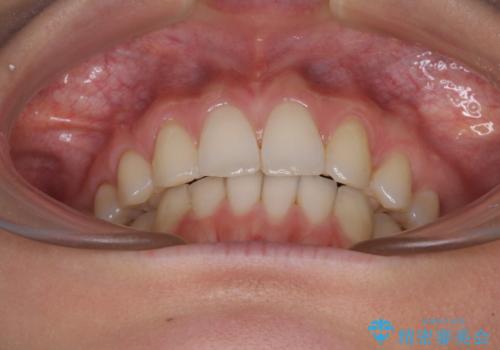

上顎前歯が2本欠損 インビザラインによる叢生の解消

- 深い咬み合わせと前歯のデコボコを気にして来院された患者様です。

上顎前歯2本が欠損しているため、妥協的なゴールを設定しインビザラインで矯正治療を行うこととしました。

上下前歯の大きさのアンバランスにより、深い咬み合わせと奥歯の咬みにくさがなかなか解決されず、治療に長期間を要することとなりました。